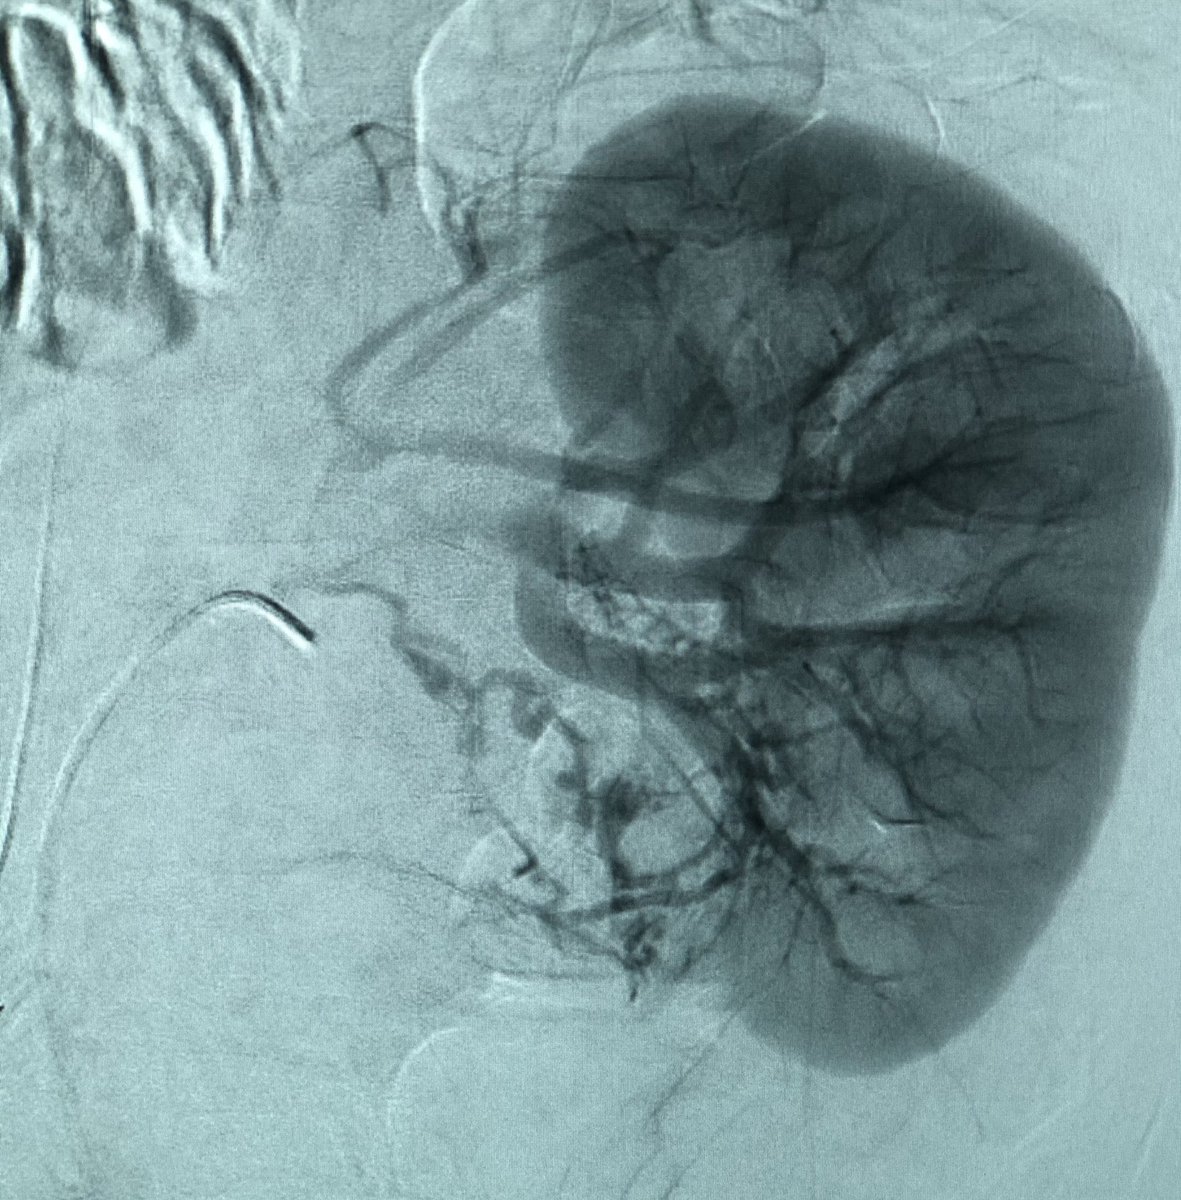

40 yo M severe L flank pain, hypotensive, admit to ICU, CT shows hemorrhage from large renal AML. Angio of torturous AML arteries, subselective run w/active🩸patient stabilized post embo, home several days later #iRad #MedTwitter #FOAMrad #PatientCare @SIR_ECS @SIRRFS @DHidlayVIR